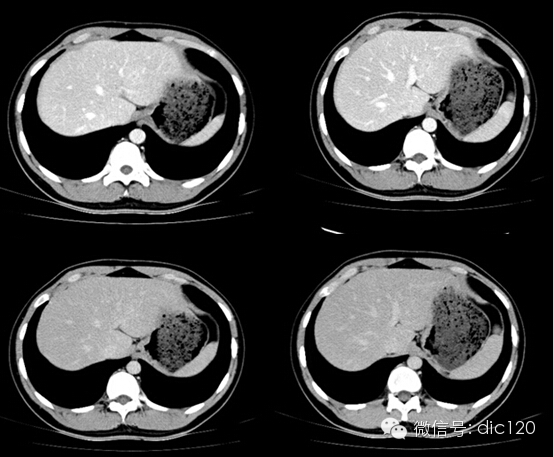

影像表現(xiàn):CT平掃與正常肝組織呈等密度,密度均勻,動(dòng)脈期病灶快速明顯均勻強(qiáng)化,中心見(jiàn)小片狀低密度影(瘢痕),門(mén)脈期及延遲期對(duì)比劑快速退出呈等密度,中央低密度影延遲強(qiáng)化。MRI腫塊T2WI為稍高信號(hào),中央高信號(hào)。動(dòng)態(tài)增強(qiáng)掃描動(dòng)脈期均顯著增強(qiáng),門(mén)脈期輕度增強(qiáng),延遲期瘢痕強(qiáng)化。

FNH具有離心性血液供應(yīng)及二條血液引流途徑。FNH的典型CT表現(xiàn)包括增強(qiáng)早期腫瘤呈彌漫均勻強(qiáng)化,在門(mén)靜脈期或門(mén)靜脈后期成等密度,病灶內(nèi)可見(jiàn)中心低密度瘢痕及輻射狀分隔,腫瘤周圍有薄而不完整的包膜樣血管。瘢痕是FNH 另一個(gè)重要影像學(xué)表現(xiàn),尤其是延遲掃描瘢痕強(qiáng)化為其特征。